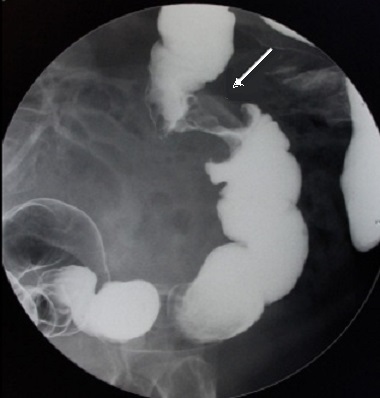

Image de lavement

baryte mono de contrast et double de contrast au

stade avance de cancer du colon est image stenosant en

circonferentiel du colon sigmoide et image laculaire

en bourgeon irregulier s'il situe au coecum

Aspect radiuologique stenosant en trognon

de pomme d'une adenome carcinoma du colon gauche

sigmoidienne .C'est image stenosant symetrique

d'une portion du colon a bord tres irregulier .

Image radiologique de lavement baryte mono de contrast |